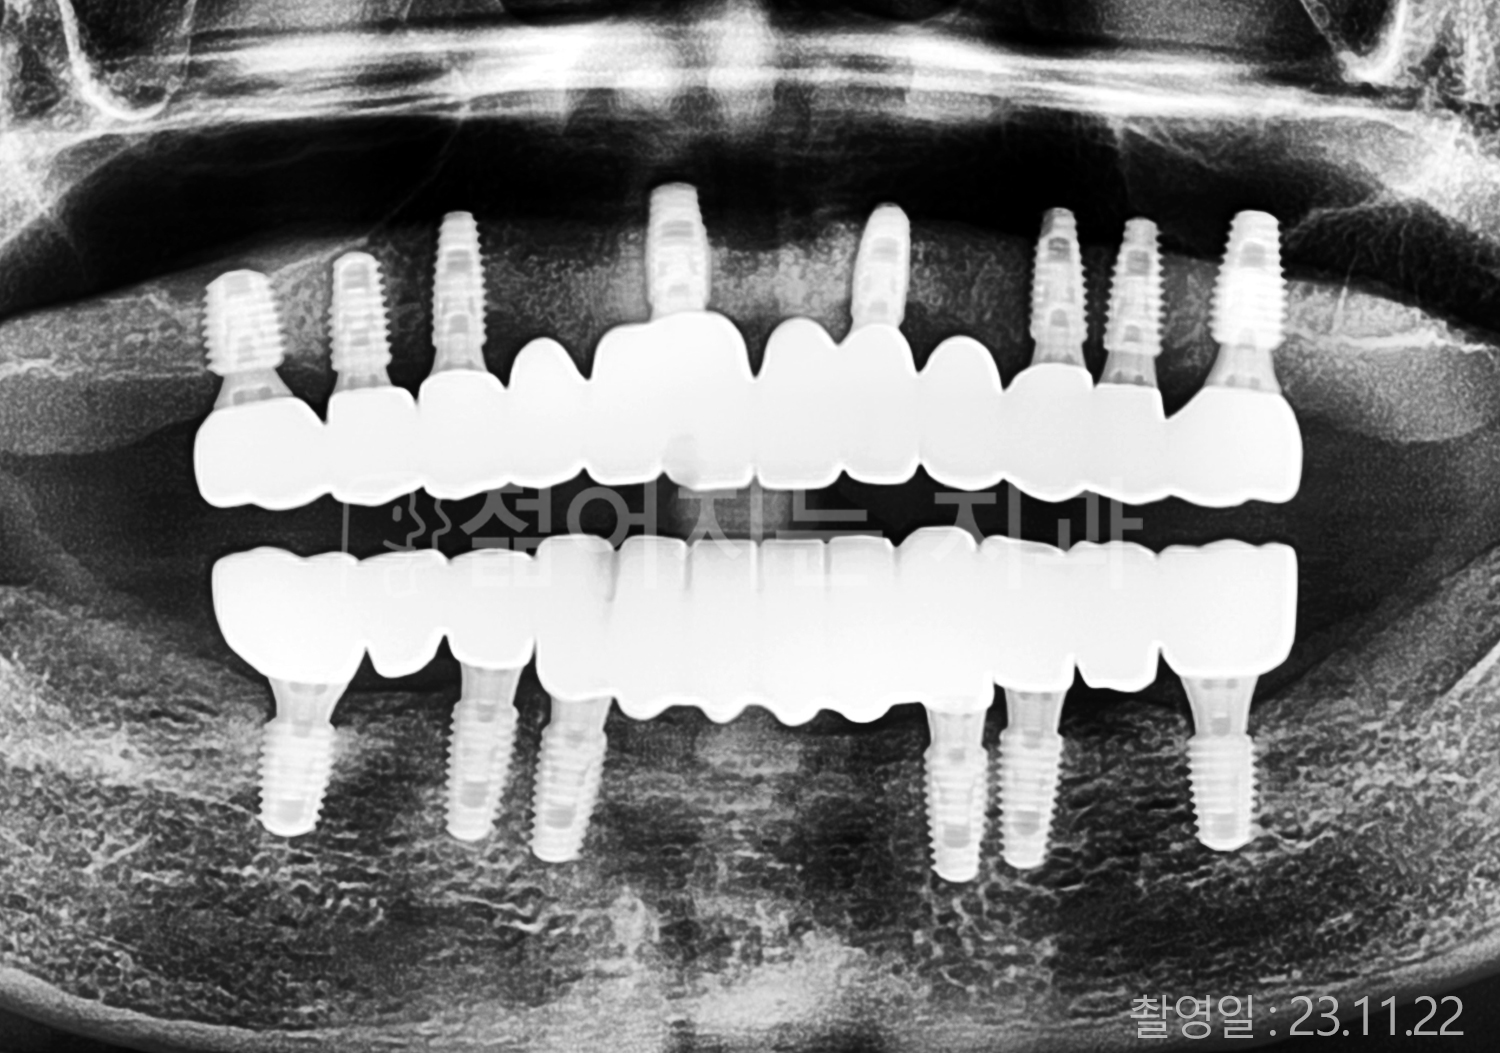

• 50대 전체치아 10개 이상 임플란트